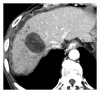

Bile leaks from the intrahepatic biliary tree are an important cause of morbidity following hepatic surgery and trauma. Despite reduction in mortality for hepatic surgery in the last 2 decades, bile leaks rates have not changed significantly. In addition to posted operative bile leaks, leaks may occur following drainage of liver abscess and tumor ablation. Most bile leaks from the intrahepatic biliary tree are transient and managed conservatively by drainage alone or endoscopic biliary decompression. Selected cases may require reoperation and enteric drainage or liver resection for management.